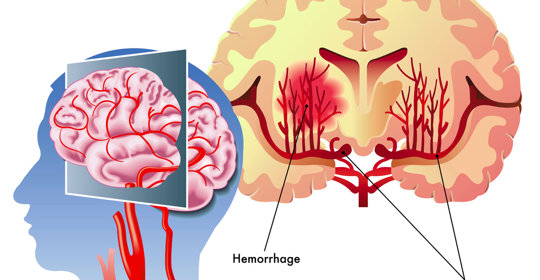

橋腦出血:中風復健方法與時間

橋腦出血:處理與預防措施

橋腦出血:治療措施與緊急性

橋腦出血:差異與治療